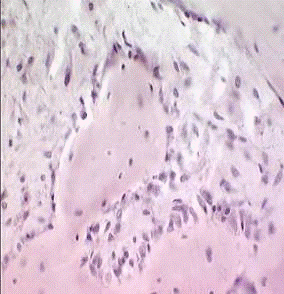

. Исследования тонкой структуры костного матрикса области регенерата

методом сканирующей электронной микроскопии (10 образцов).

2. Исследования тонкой структуры костного матрикса области

регенерата методом атомно-силовой микроскопии (10 образцов).